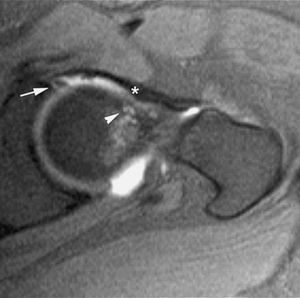

Fig. 4.--Síndrome de choque fémoro-acetabular. Corte axial oblicuo de RMA potenciado en T1 con técnica de supresión grasa que muestra una deformidad en la transición cabeza-cuello femoral con edema focal (cabeza de flecha), formación de pequeño quiste sinovial (herniation pit), rotura del labrum antero-superior (flecha) y engrosamiento del ligamento ilio-femoral (asterisco).